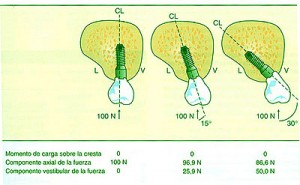

REF: SEGUNDA ENTREGA DEL CURSO: ANATOMÍA OCLUSAL INDIVIDUAL — ABBUTMENTS ANGULADOS POR IMPLANTES INCLINADOS Las piezas dentarias presentan un diseño biomecánico que a partir de su perpendicularidad a la Espiral Dinámica (Willams Mc Horris .Visión tridimensional de la Curva de Spee y de la Curva de Wilson.) reciben las fuerzas de manera axial al hueso receptor. Aplicando técnicas de análisis tridimensionales de elementos finitos y métodos fotoelásticos se ha podido comprobar que cuando se aplican cargas anguladas se producen grandes tensiones a nivel de la cresta ósea.(Misch). (Tomado de Misch) Con una angulación entre 0º y 15 º del abuttment la concentración de tensiones en la zona de la cresta es similar. — ALTURA DE LA CORONA Otro concepto importante es la Relación Corono – Implantaria. Sabemos que debido a la pérdida en altura del hueso es frecuente observar que el largo coronario supera el largo de la implantación endo ósea, situación que es según Misch, mas comprometida en importancia a la de la angulación del abbutmentt , provocando mayores reabsorciones crestales en el caso de recibir fuerzas no axiales. De la misma manera que en la oclusión dentaria, esta situación es manejable en Implantología actuando de manera axial sobre la pieza implantada o dentaria para que las fuerzas recaigan sobre el eje implantario o dentario. En ese sentido es importantísima la situación de los Contactos Interoclusales de manera Tripódica para mantener la Axialidad y sobre todo la Estabilidad de la Oclusión supra Implantes. Misch encuentra útil utilizar coronas de baja Altura Cuspídea incrementando el surco central dos o tres milímetros, con lo cual desde mi punto de vista no solo se disminuye la Eficacia Masticatoria, sino que se acerca al concepto de Céntrica Larga lo que a mi juicio incrementa el juego muscular e induce al Bruxismo.- En cuanto al contorno coronario, debido a que la mayoría de los Implantes tienen una plataforma menor en su emergencia que la que presentan la piezas naturales, es lógico reducir dichos contornos para evitar atrapamiento de alimentos y lograr una correcta fisioterapia natural de la encía peri implantaria. Es por eso la “Premolarización “ un recurso adecuado ya que recordemos que un premolar contiene en su estructura Oclusal la mitad de los componentes anatómicos de un molar los que aún así, cumplen con los conceptos de una OCLUSIÓN ORGANIZADA. REF: SEGUNDA ENTREGA DEL CURSO: ANATOMÍA OCLUSAL INDIVIDUAL Lo importante es que la plataforma del Implante se encuentre debajo de la resultante de las fuerzas axiales. Como dijimos es fundamental relacionar la anchura coronaria con el diámetro de la plataforma del Implante.(Misch). Crestas Estrechas Crestas Estrechas Premolarización Sin embargo si se tiene en consideración el Área Funcional Oclusal (de punto de contacto A a punto de contacto C (45% de su ancho total coronario), observaremos que la reducción coronaria en sentido vestibulo lingual o palatino, no altera la Eficacia Masticatoria ya que las áreas coronarias periféricas a la zona funcional solo sirven para conducir el alimento hacia la inserción del Implante produciendo el masaje fisiológico del alimento , y como la superficie de emergencia es menor que en un diente, lo que se conserva es la parte auténticamente necesaria y funcional de la cara oclusal. Funcionalidad Molar en el Plano Frontal REF: SEGUNDA ENTREGA DEL CURSO: ANATOMÍA OCLUSAL DE CONJUNTO EN EL PLANO FRONTAL Para obtener Axialidad en hueso Div. A es preciso conservar perpendicularidad entre el Implante y la Fosa Central de la Corona, pero a mi juicio, eso solo debe tener una recepción de la carga mediante puntos de contacto equilibrados preferentemente Tripódicos, ya que es el Tripodismo el esquema mecánico básico de estabilidad en la Física Mecánica. En el hueso Div . B –C y D ese eje debe lingualizarse dado el sentido de la reabsorción que se produce. (Tomado de Misch) Oclusion implanto asistida 1ª parteBinderman en un estudio de elementos finitos realizado en la década del 70, concluyó que todos los diseños de Implantes estudiados soportaban menor tensión si la carga era axial al eje mayor del Implante.

A partir de 15º estas tensiones se incrementan en un 50 % o más en la zona vestibular.